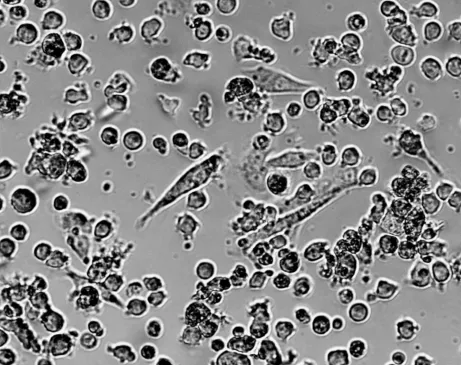

THP-1单核细胞正常形态为悬浮的体积较小、透亮的圆形细胞,少数聚团成葡萄状,粒粒饱满,轮廓清晰。该细胞在偏酸性环境中,生长更快,所以当培养基稍微变黄(呈橘红色)时,是比较适合细胞生长的,此时补液或半换液即可。开启后的1640培养基,长期放置pH会偏高,建议开封后一周内使用完毕。该细胞对血清要求高,血清质量差异可能引起细胞状态变化,建议选用高质量的胎牛血清。

图1 THP-1细胞ATCC参考正常形态图